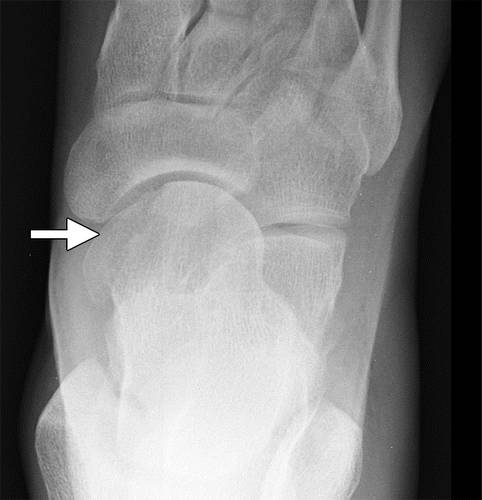

在距骨头骨折通常显示在足的AP、斜、侧位片。 在所有视图上仔细评估距骨头的轮廓,以评估细微的断裂和位移(图3)。 在识别或怀疑距骨头部损伤后,应进行CT以评估位移和旋转程度以及对于颈部的潜在延伸。

图3a距骨骨小头骨折。 足部的AP射线照片(a)和斜轴重新格式化的CT图像(b)显示了距骨头部(箭头)的微小位移剪切断裂。